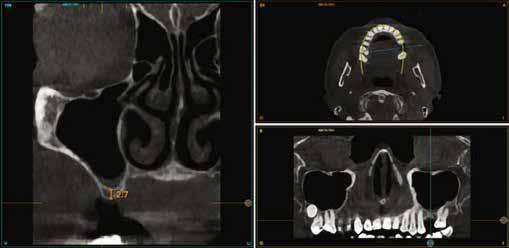

A CT metszetekben a 48-as gyökerei körbeölelik a canalis mandibularist, amelyet piros nyíllal jelöltünk a fotókon.

Szeretnék mutatni néhány ábrát az egyik bonyolult esetről, a közelmúltból. A CT-n látszik, hogy a három gyökér teljesen „körbenőtte” az ideget. Van olyan frontális metszeti kép, ahol csak a gyökerek vannak a nervus körül, ezen a szakaszon egyáltalán nincs meg a csontos fala a canalisnak. Szeparációs technikával, viszonylag könnyen, minimális traumával, szövődménymentesen sikerült eltávolítani a fog minden részét. A várakozásnak megfelelően, a beteg nem számolt be paraesthesiáról.